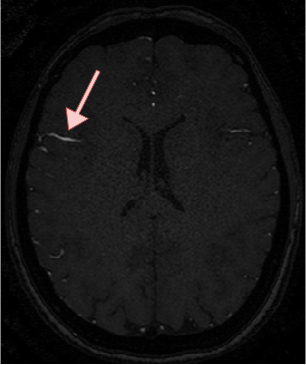

4.4 Qualitative Results

We show sample visual results of representative slices in Figure 3. Sample 3D visual results are given as surface renderings of segmentation maps in Figure 4.

| Baseline GAN | sGAN | Ground Truth | |

|---|---|---|---|

![]() |

|